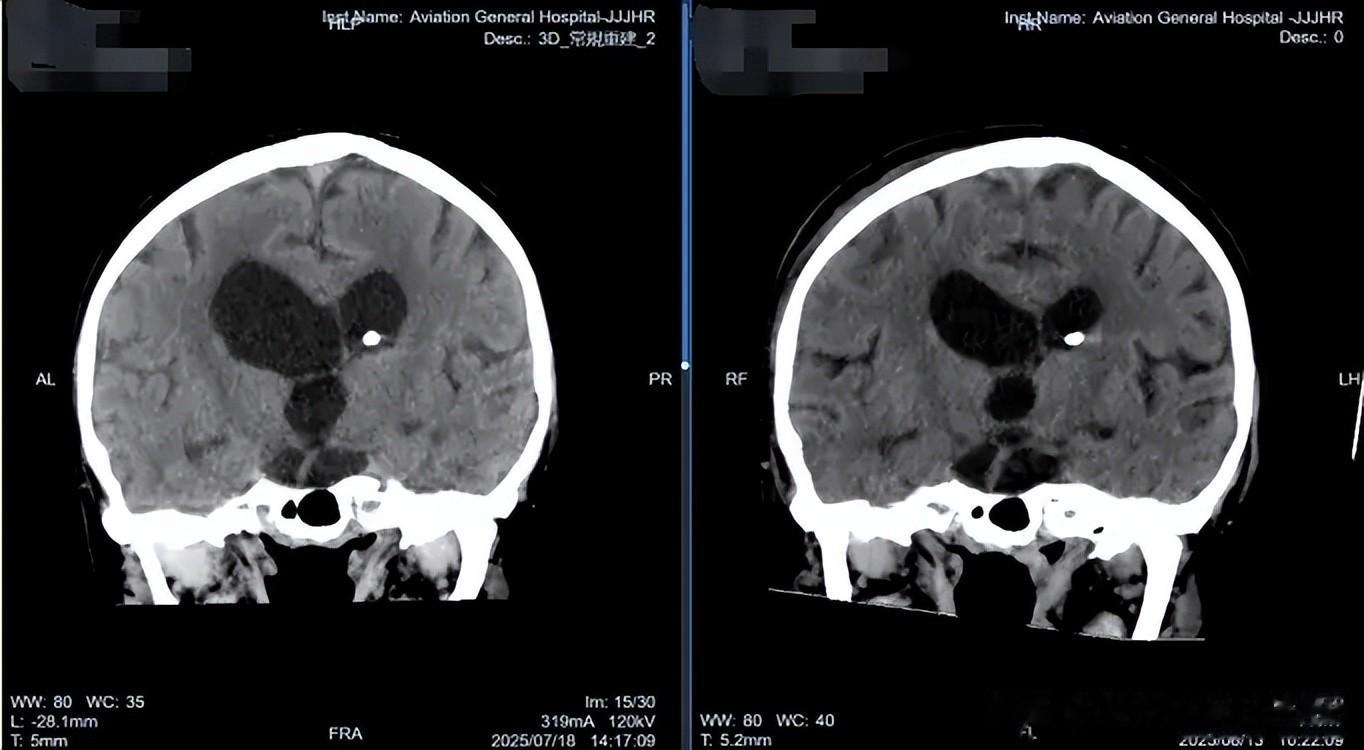

软性神经内镜术前术后对比

术后,王先生的脑脊液 NGS 检验提示大肠埃希菌感染,肖庆教授团队迅速调整抗炎治疗方案,同时密切监测脑脊液情况,逐步抬高、关闭外引流。在医护人员的精心照料下,王先生的病情稳步好转,头晕、头痛症状完全消失,四肢活动自如,未遗留任何神经功能缺损。复查CT显示脑室系统较前缩小,脑脊液循环恢复稳定。随后,肖庆教授团队成功为王先生行脑室分流管去除术,历经31天的精心治疗与康复,王先生终于摆脱了牵制他大半生的分流管。